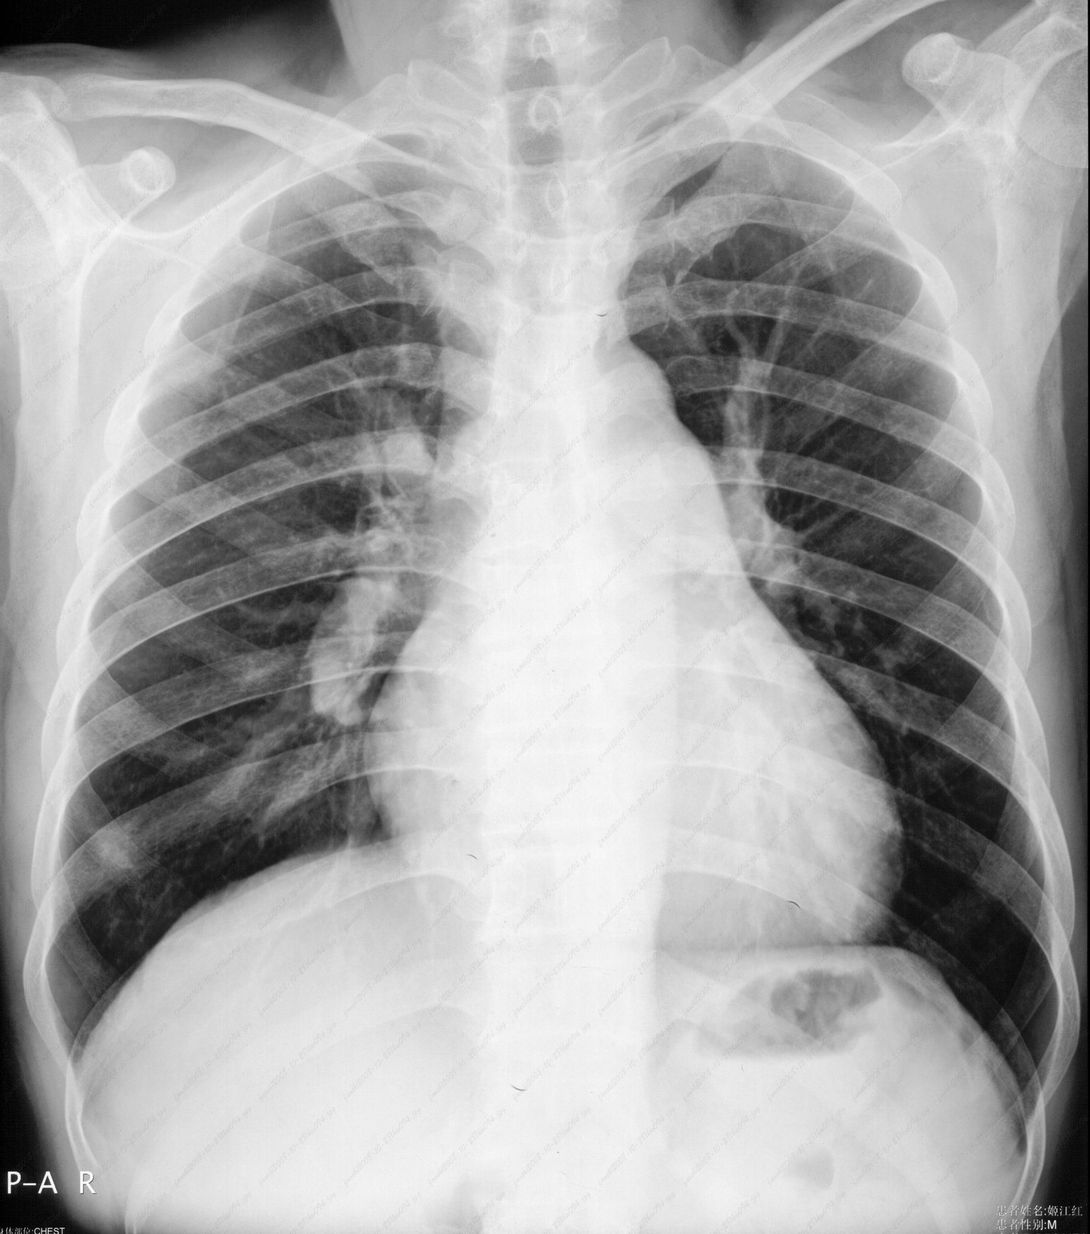

男性,47岁。胸部不适一年,ct检查发现右胸膜下结节。http://www.radida.com/bbs/forum.php?mod=viewthread&tid=46094

右下肺前胸膜下小结节,强化不明显。建议定期观察!

病灶周围似有纤维化征像,增强明显强化,但中央可见点状低强化区,考虑慢性病变可能如炎性假瘤等,病灶边缘部分毛糙有切迹,双侧胸腔少量积液影,不除外恶性

结节未见明显强化,局部胸膜增后粘连,内缘纹理影增重伴小围星灶,局部胸膜下小三角状实变影,尖端见纤维索牵扯征,综合考虑炎性病变,有增殖表现,不出外tb灶

右肺中叶外侧段胸膜下结节状病灶,性质待定(不排除周围型肺癌可能)。

右前胸膜下小结节,边缘有小纤维条索影与胸膜粘连,考虑如炎性假瘤之类慢性病变可能。期待二周后的结果。

小结节的周围似乎与斜裂的走行有关,边缘分界不很清楚,与侧胸膜关系密切,有轻度强化,不能除外恶性,建议密切观察。

右下肺胸膜下小结节,强化不明显。建议定期观察!

汇报临床诊断:右肺动脉分枝栓塞

右肺静脉充盈缺损,左心房体积小,右肺动脉远端动脉充盈缺损,右肺血管影细小,考虑;右肺动脉远端栓塞.